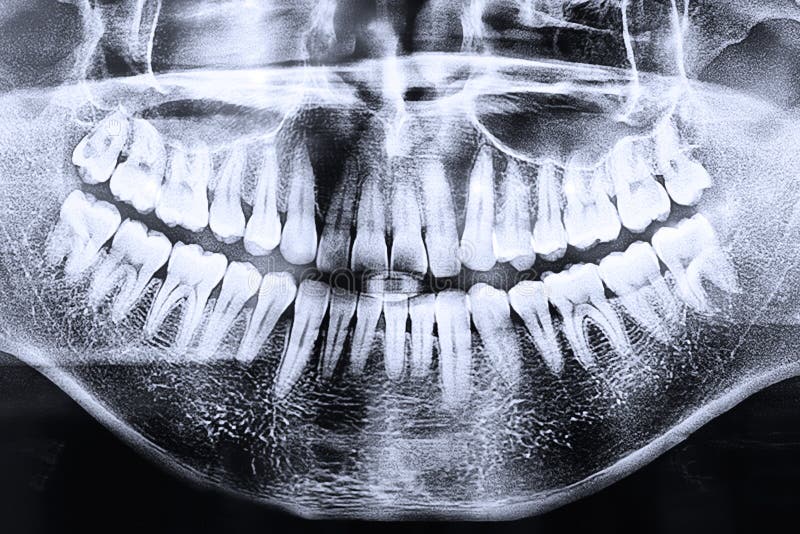

Стоматологические Исследования: Рентген Инвагинации Зубов